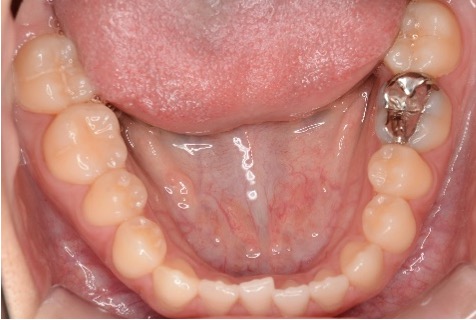

術前

術後